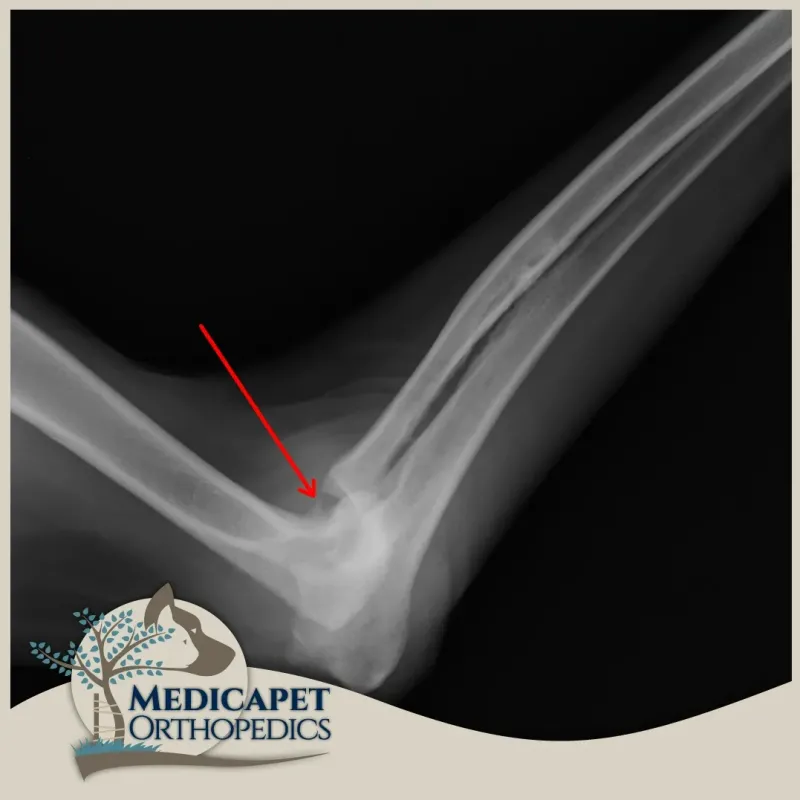

Dirsek çıkığı, genellikle ulnanın eklem içindeki pozisyonundan ayrıldığında meydana gelir. Bu, doğuştan gelen bir durum veya travma sonucu olabilir.

Teşhis, dirsek ekleminin fiziksel muayenesi ve palpasyonu yoluyla yapılır. Travmatik çıkık oluştuğunda hastalar genellikle ilgili bacak üzerine ağırlık vermek istemezler ve sıklıkla bacağı vücuttan uzakta ve kısmen fleksiyonda tutarlar. Fizik muayenede ağrılı bir eklem bölgesi ve anatomik pozisyonda bozukluk görülür. Çıkığı doğrulamak için radyografi kullanırız.